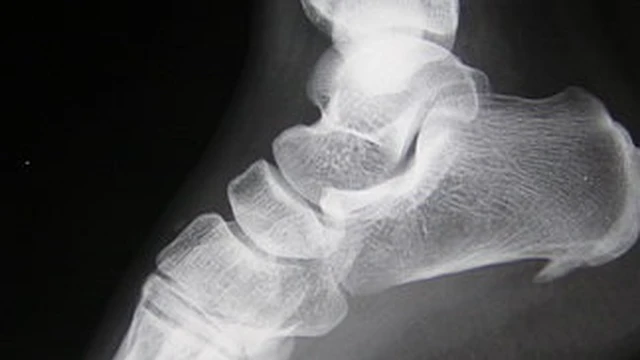

Gai xương gót là tình trạng đau nhức ở gót chân, khiến cho bạn khởi động ngày mới với sự đau đớn, khó chịu. Vậy đâu là nguyên nhân gây ra bệnh gai xương gót? Triệu chứng gai xương gót là gì và cách điều trị như thế nào? Hãy cùng Long Châu theo dõi bài viết dưới đây nhé.